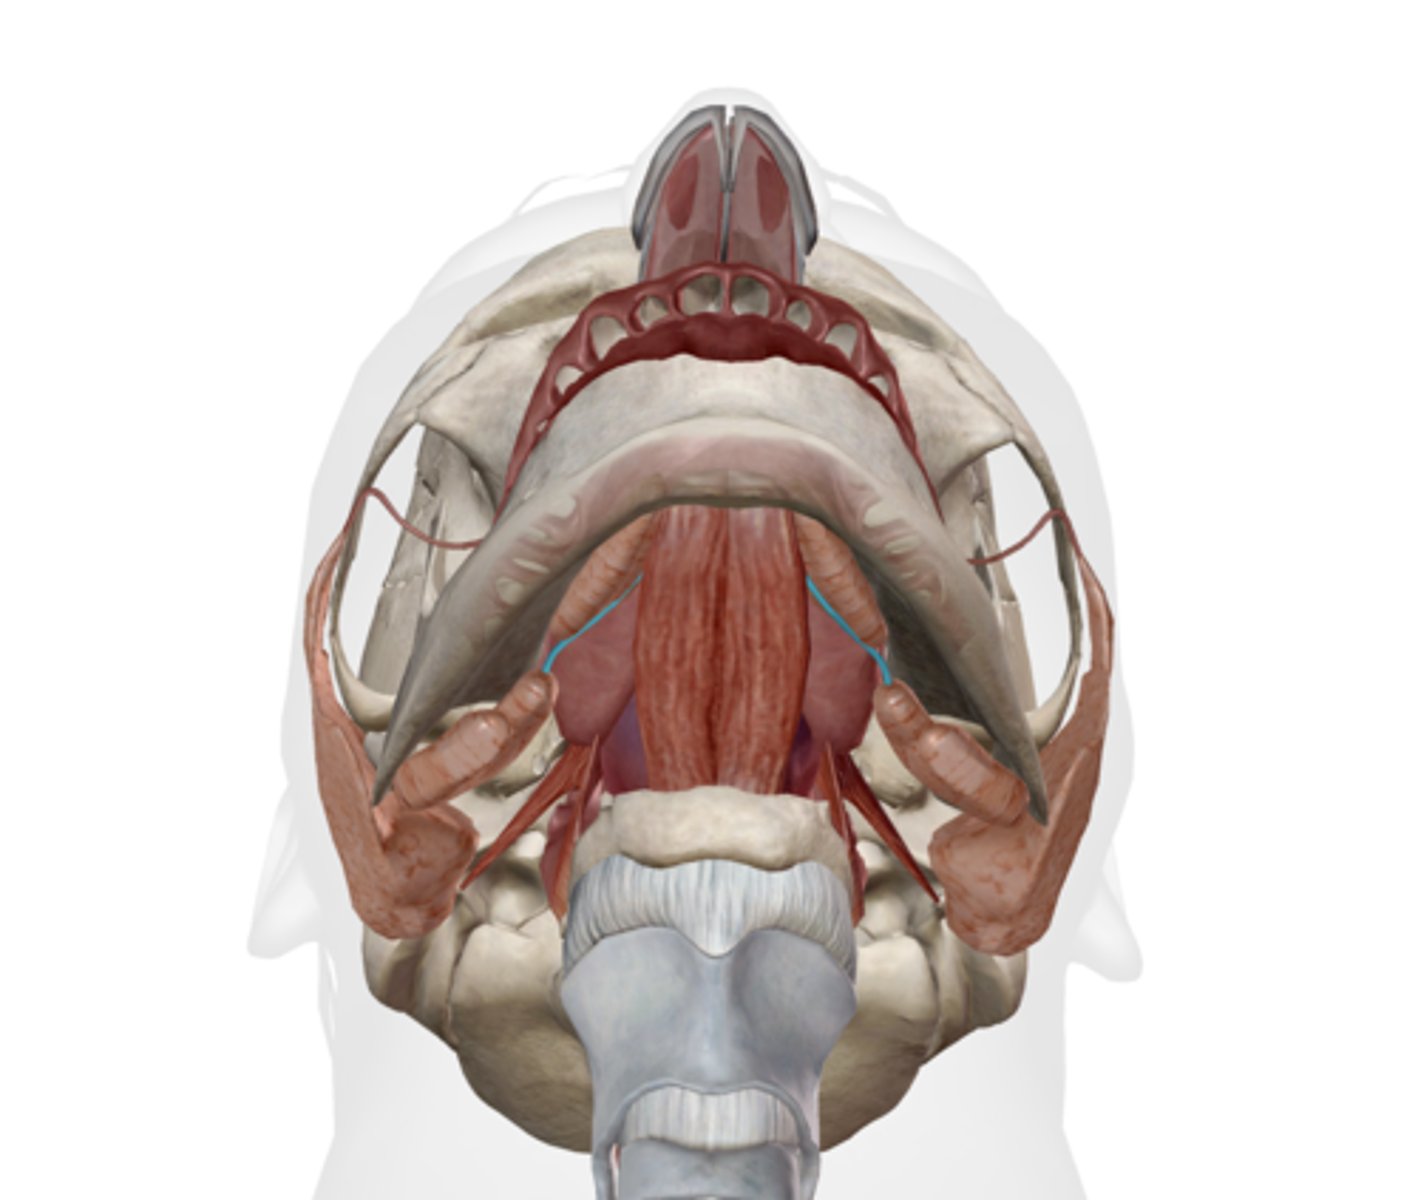

Submandibular duct

Sublingual gland